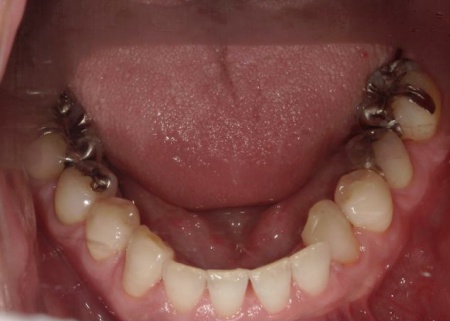

・前歯の噛み合わせ

下前歯が上前歯より前に出ている「反対咬合(こうごう)」で、将来的に歯や顎への負担が生じるリスクがあります。

・矯正治療

前歯の反対咬合については、部分矯正で改善を図ります。

前歯の噛み合わせ治療では、上顎の内側に歯を内側から動かす装置「リンガルアーチ」を装着します。併せて、上前歯の表面に「ブラケット」と呼ばれるボタン状の装置を接着し、そこにワイヤーを通して歯を動かす「マルチブラケット装置」を用いて部分矯正を行いました。